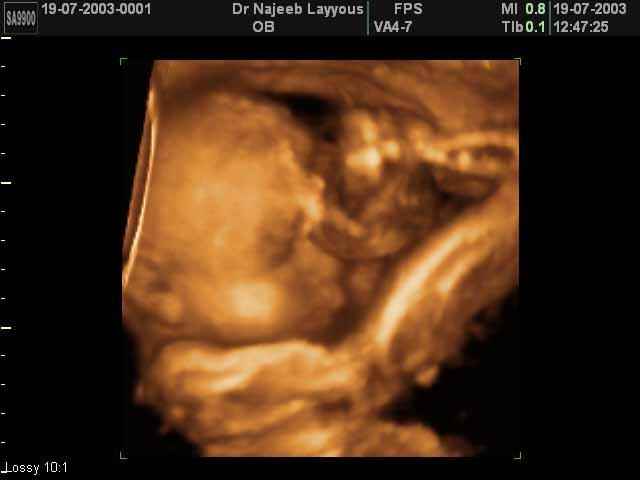

- 3D Fetal Profile Ultrasound Scan Photos

3D Fetal Profile Ultrasound Scan Photos | Dr N Layyous